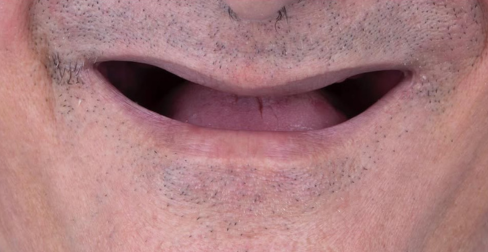

Some of Our Cases